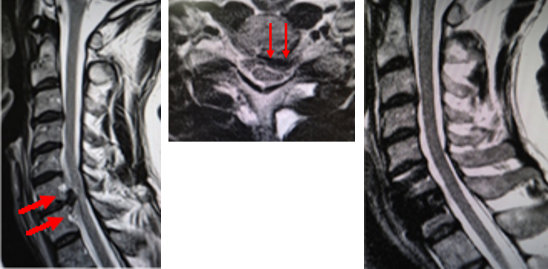

図(左、まん中)術前MRI:首の骨の間のクッション(椎間板)が脊柱管へ飛び出し、脊髄を強く圧迫しています。

(右)術後MRI:飛び出した椎間板を摘出し、脊髄の圧迫が解除されています。